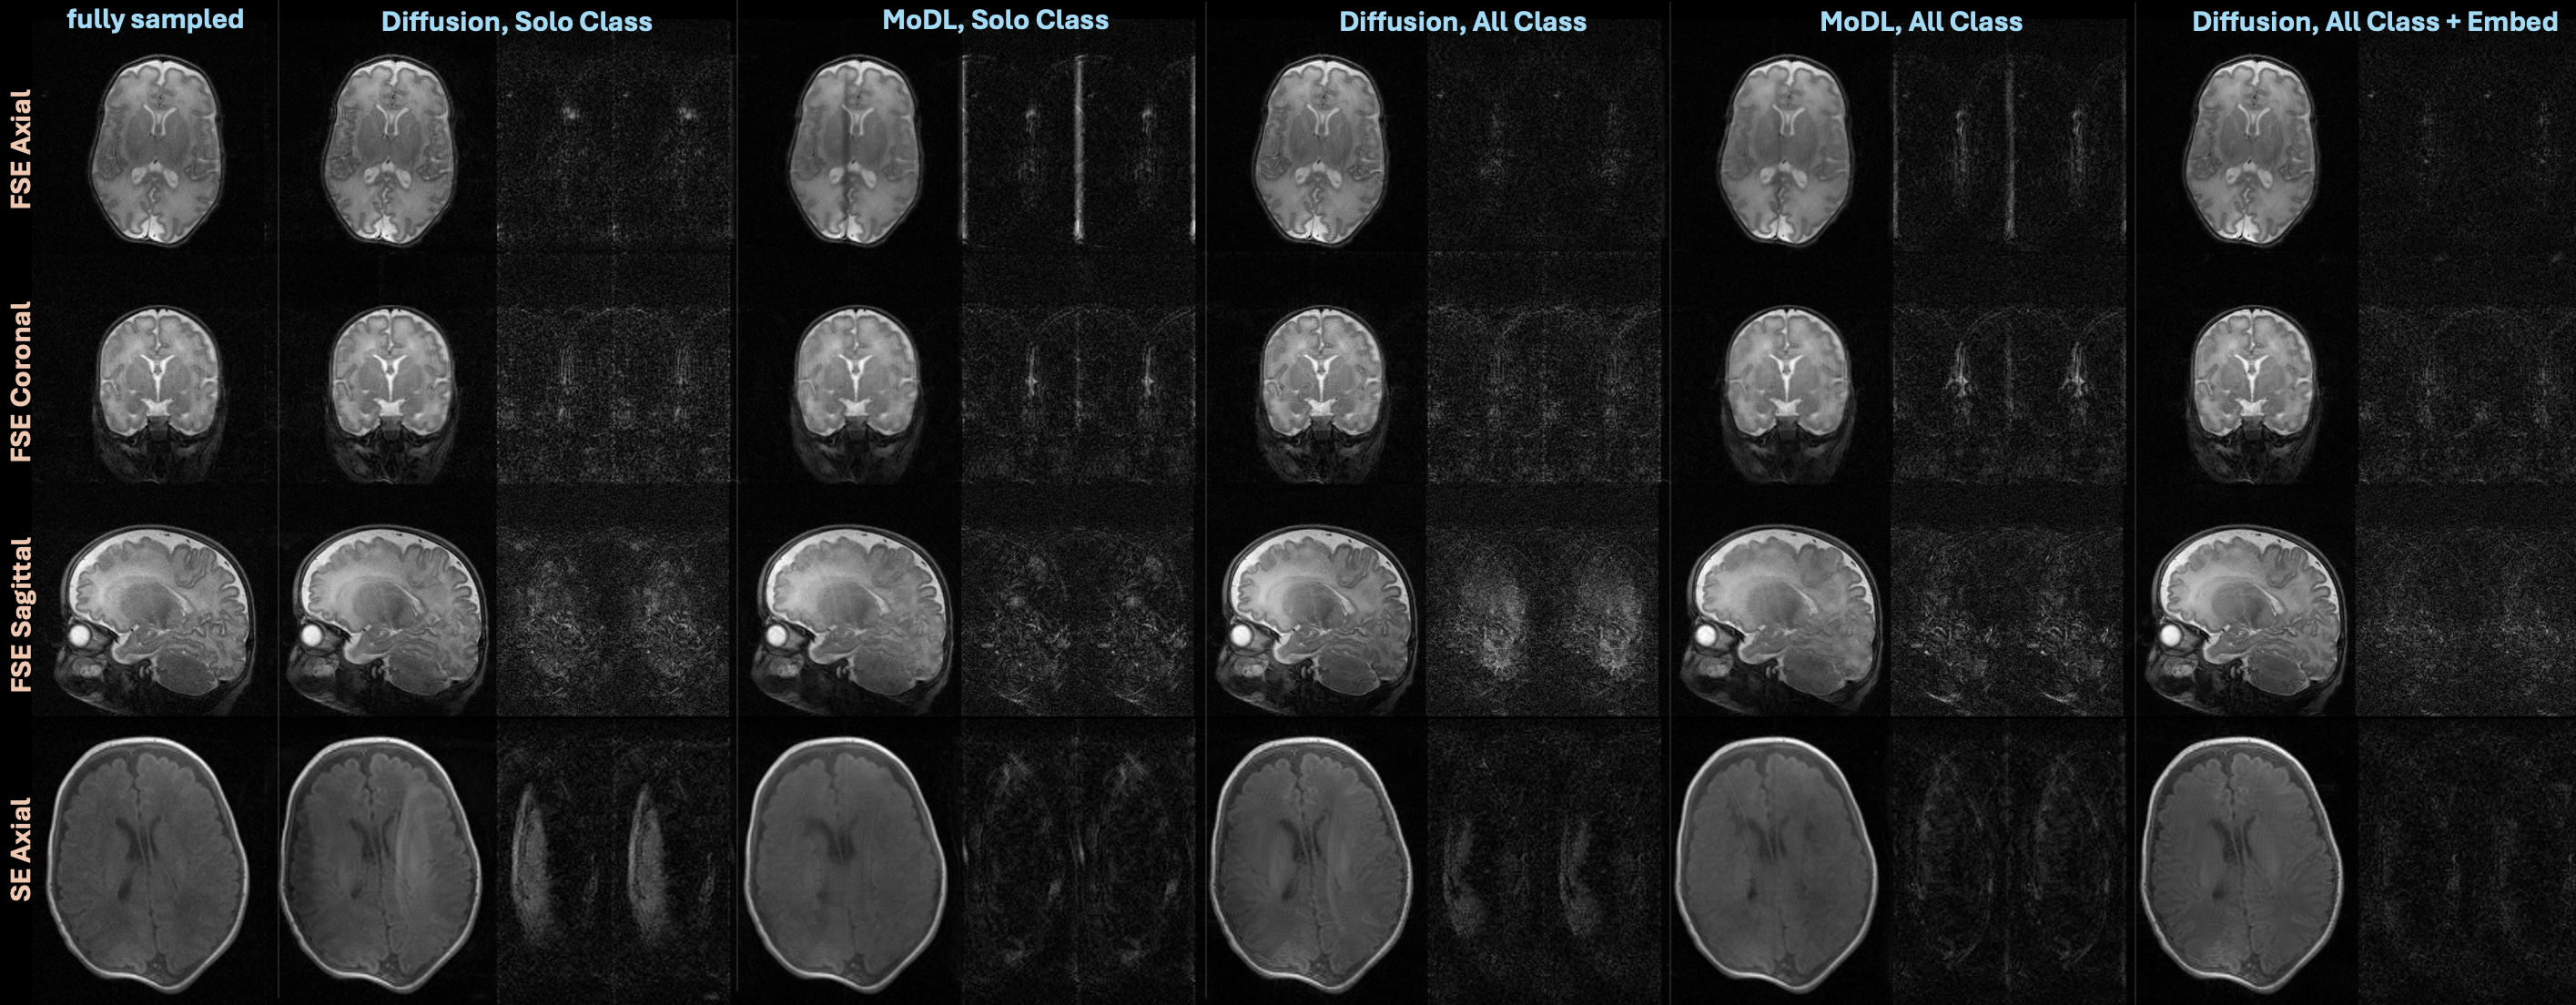

Supporting Figure S1 compares reconstructions from the generative models with the end-to-end MoDL models trained on each image class separately or trained on all data simultaneously with violin plots, and Supporting Figure S2 shows example reconstructions on all four image classes.

Since previous literature extensively compares generative models to other state-of-the-art methods for accelerated MRI reconstruction (37, 26, 30), this manuscript focused on analyzing our contributions in developing a novel pipeline for training generative models on our in-NICU neonatal MRI data and performing the first clinical validation of generative models for accelerated in-NICU neonatal MRI. However, for the interested reader, Supporting Figures S1 and S2 show that generative models trained with the proposed framework achieve competitive quantitative reconstruction performance in comparison to MoDL, a state-of-the-art end-to-end method. We suspect ModL performed worse on the axial images because the test dataset consisted of different under-sampling patterns and matrix sizes from the training data (since we under-sampled by throwing away groups of echo trains which varied across the test set), which ModL perhaps did not adapt well too. Future research directions could develop methods to most effectively train end-to-end methods for accelerated in-NICU neonatal MRI. Note, generative methods provide the additional benefit of applying to other measurement models without re-training, like motion correction described in the previous paragraph.

Supporting Figure S1: Quantitative NRMSE results on all four image classes comparing reconstructions on under-sampled data using a Diffusion model trained on just the image class, ModL trained on just the image class, Diffusion trained on all classes, MoDL trained on all classes, and the proposed diffusion framework trained on all data with class embeddings.

Supporting Figure S2: Examples reconstructions on all four image classes comparing reconstructions on under-sampled data using a Diffusion model trained on just the image class, ModL trained on just the image class, Diffusion trained on all classes, MoDL trained on all classes, and the proposed diffusion framework trained on all data with class embeddings.